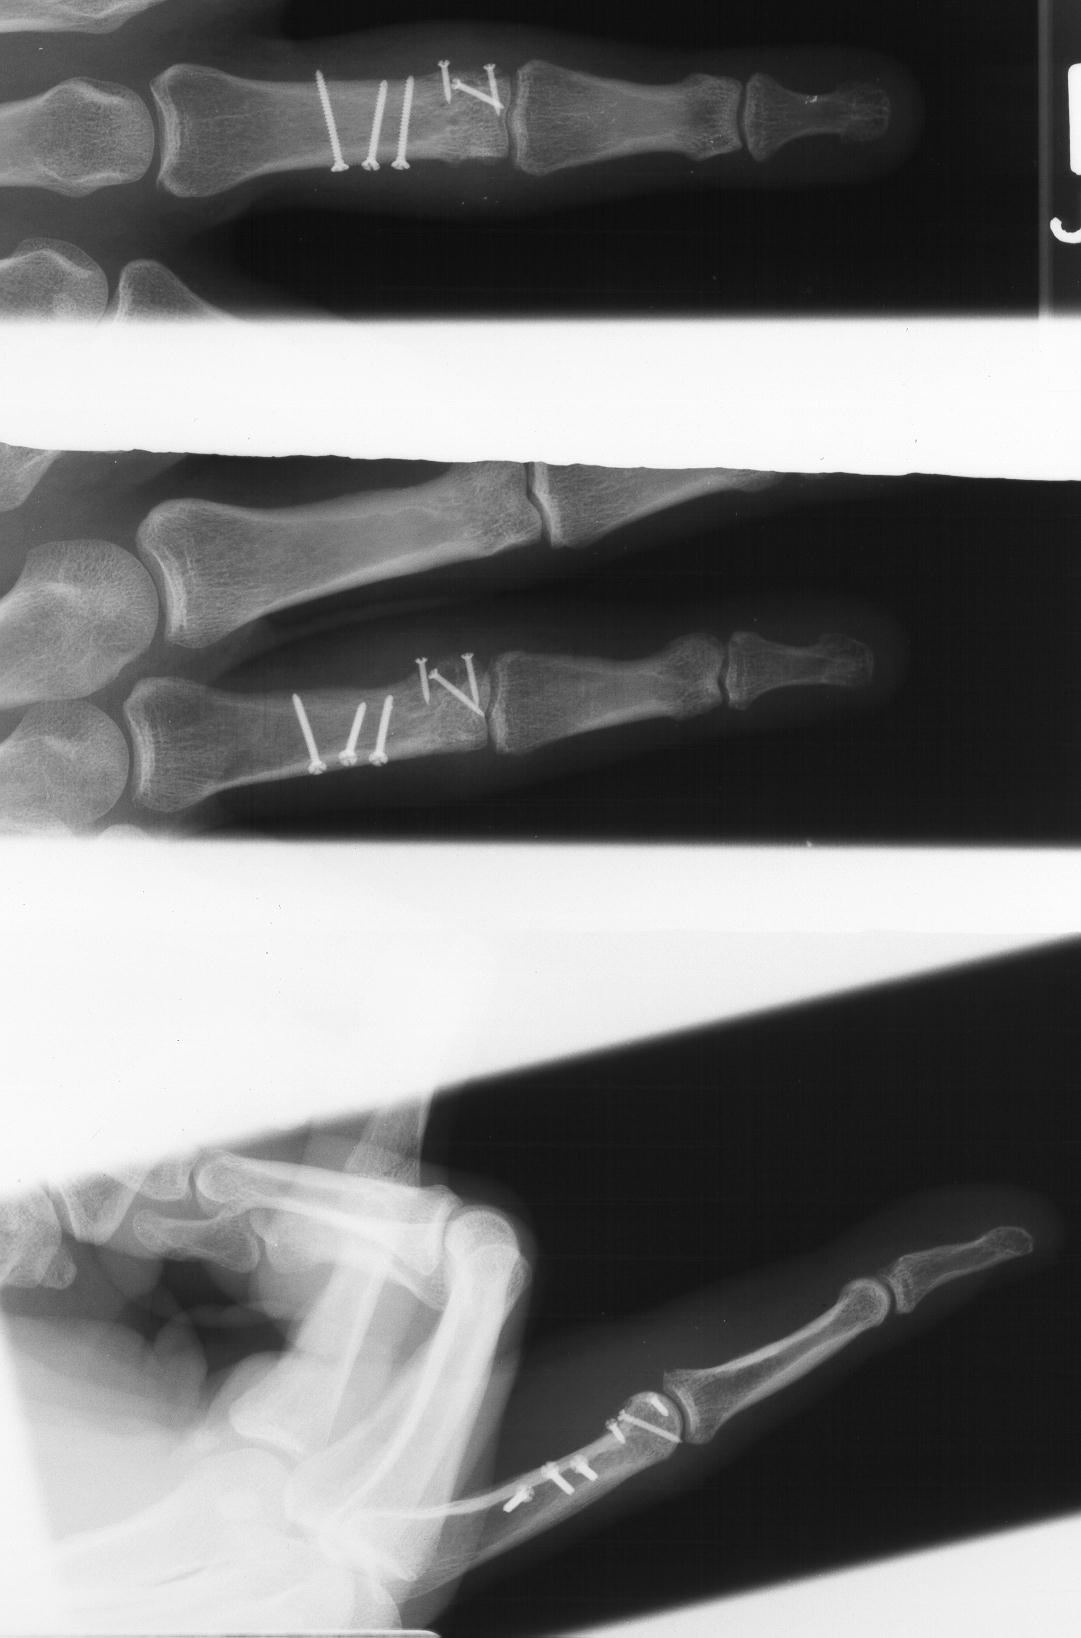

The joint was reconstructed with 1.0mm screws and the shaft fixed with 1.3mm screws using the Synthes titanium modular hand tray.

Six months after surgery: